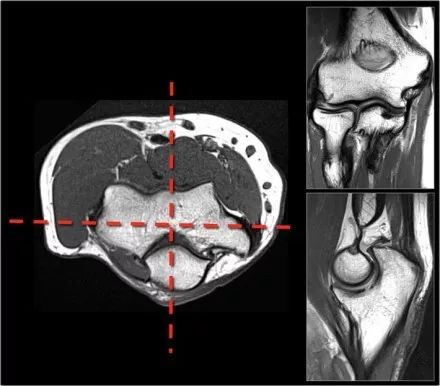

需要确保以标准化的方式正确地获得成像平面,在轴向定位器上使用肱骨髁的轴来规划冠状扫描,矢状图像垂直于冠状扫描进行扫描。

通过这种方式,获得良好的图像,这些是我们所习惯正常的解剖结构